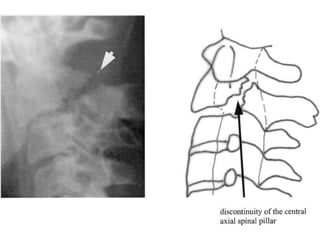

Hangman #

Described by Schneider et al in 1965

Bilateral # at the Pars interarticularis of C2 +

Traumatic subluxation of C2 on C3

Levine classification 1973

• type I: fracture with <3 mm antero-posterior deviation

• no angular deviation

• type II: fracture with >3 mm antero-posterior deviation

• significant angular deviation

• disruption of posterior longitudinal ligament

• type IIa: the fracture line is horizontal/oblique (instead

of vertical)

• significant angular deviation without anterior translation

• type III: type I with bilateral facet joint dislocation